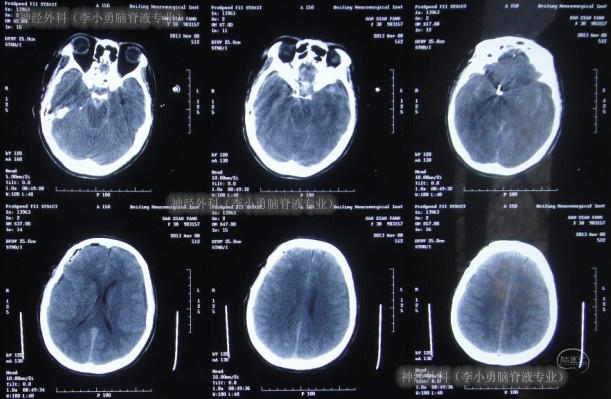

2013年11月11日即术后7天时,患者中度昏迷,伴有呼吸困难,立即进行头颅CT检查发现了脑严重肿胀的表现(图-4)。

图-4:术后7天头颅CT